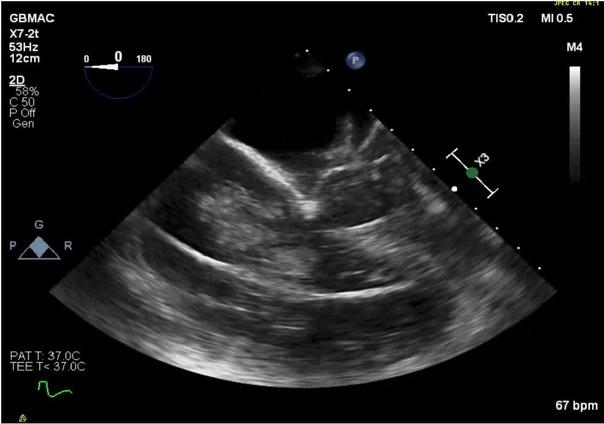

Amidst continuous resuscitation efforts, a pericardiotomy was performed to allow direct manual heart compressions. TEE revealed a large clot, obstructing the right atrium and most of the right ventricle, with a smaller clot in the pulmonary artery, almost completely blocking forward flow (Figure 4; Online supplementary video 4).

Fig. 4

Large clot, obstructing the right atrium and most of the right ventricle, with a smaller clot in the pulmonary artery